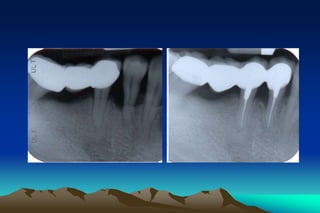

Palato-gingival groove

* Developmental abnormality

* A funnel for the accumulation of plaque

and calculus in the depth of groove

* Prevalence on incisors ranges from 1.9 %

to 4.4 %

Palato-gingival groove * Developmentalabnormality * A funnel for the accumulation of plaque and calculus in the depth of groove * Prevalence on incisors ranges from 1.9 % to 4.4 %

• 58.

Cervical enamel projections *Rapidprogression of pocket formation (precluding an organic connective tissue attachment) *Hemidesmosome attachment in CEJ  less resistant to breakdown by bacterial plaque  rapid progression of disease